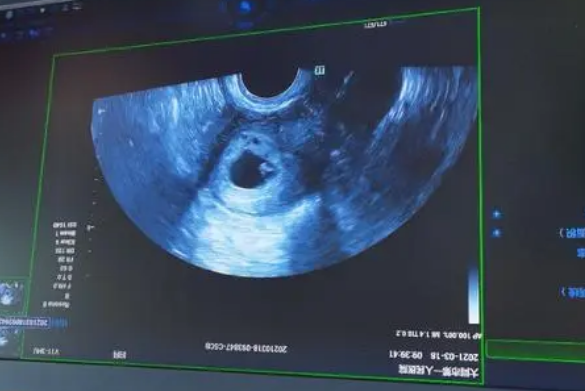

问题描述: 我目前已经做了试管移植了,算了下时间差不多有一个月了,然后今天的时候我去医院做检查发现有胎心但其他数值不好,对此其实我是比较焦虑的,虽然医生给我开了一些药物,但是我还是不太放心,因此我想问问这种情况具体该怎么保胎呢?

2、定期检查与监测:定期进行超声检查和血液检查,可以及时了解胚胎的发育情况和激素水平,如果发现数值持续不佳,医生可能会建议进行更深入的检查,如基因检测等,以便找出潜在的问题并制定更精准的治疗方案。